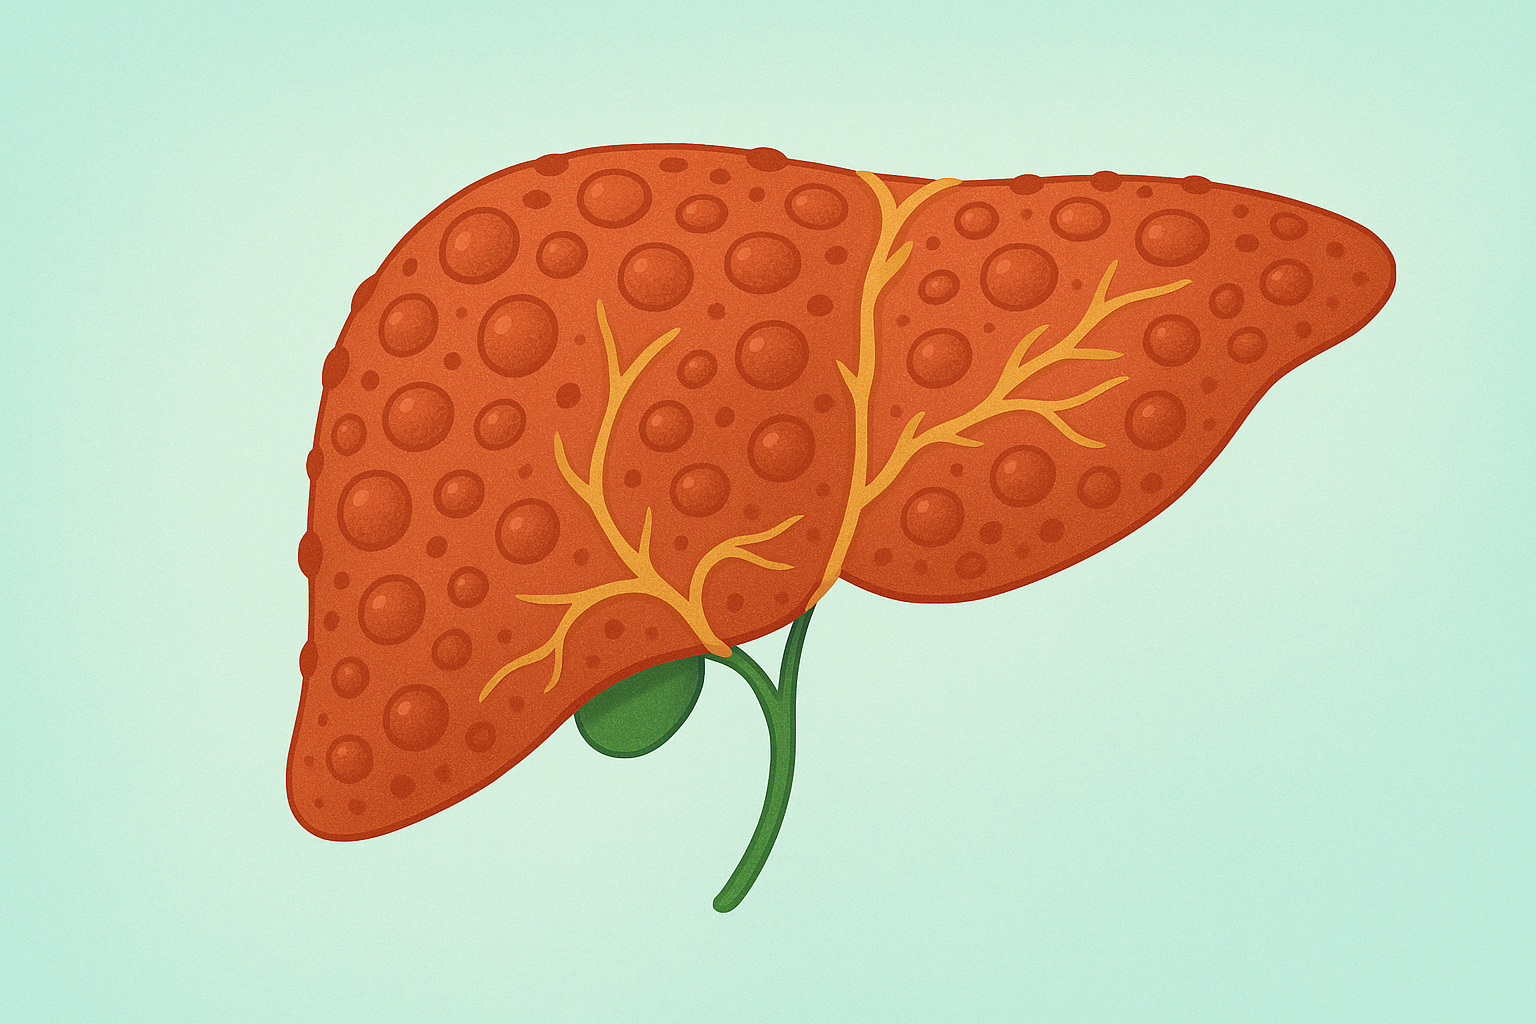

Niveau 2: Pathologie

Formation de 332 heures pour entrer au cœur des mécanismes de la maladie.

Comprendre comment une pathologie naît, évolue, perturbe les équilibres physiologiques… et apprendre à construire une réflexion thérapeutique solide, structurée et stratégique.

Programme reconnu par l’ASCA (cycle 3) et la RME.